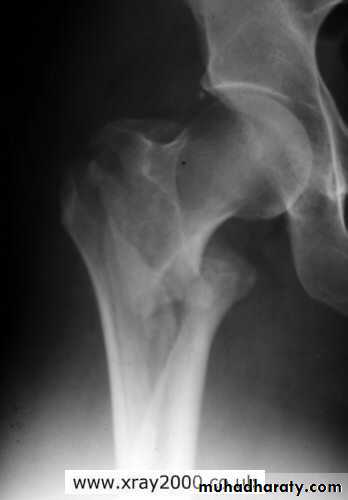

Posterior dislocation:

Mechanism of injure:4 out of 5 traumatic hip dislocations are posterior.

Usually occur in road traffic accident when the knee striking the dashboard

the femoral head is forced out of its socket sometimes associated with fracture.

Clinically:

In a straight forward case the diagnosis is easy.O\E

Leg is short, internally rotated, adducted ,

and slightly flexed hip.

and with femoral fracture to include both the hip and knee.Radiological examinations

X-R AP view we can see the dislocation with or without associated fracture posterior wall of the acetabulum,or fracture head of the femur,

And neck of femur.